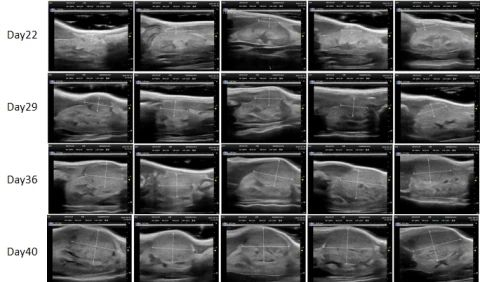

2. B³¬ÊÖÒÕ

ʹÓó¬Éù¶àÆÕÀպͳ¬Éù»Ø²¨Ô­Àí  £¬¿ÉÒÔÏÔʾ³ö¾Ö²¿ÓÐʵÖÊÐÔµÄÖ×Áö  £¬ÌØÊâÊÊÓÃÓÚÉöÔà¡¢ÒÈÏÙ¡¢Âѳ²¡¢°òë׵Ȳ¿Î»µÄԭλÖ×ÁöÄ£×Ó¼à²â¡£

• 3. ԭλÂѳ²°© PDXM-271O

¶¯Î´ÆÐÔÂãÊó

PDX£ºPDXM-271O

×éÖ¯ÀàÐÍ£ºÂѳ²

Ä£×Ó½¨É裺ԭλֲÈëÖ×Áö×éÖ¯¿é

³ÉÏñ£º³¬Éù£¨L38-22  £¬30MHz£©

3 ԭλÂѳ²°© PDXM-271O -1.jpg

3 ԭλÂѳ²°© PDXM-271O -2.jpg